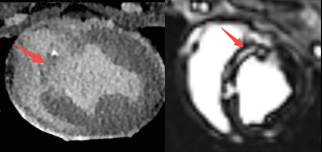

恍惚之间,是否只觉此为MRI?

上述二图,皆出自同一人、同一种、同一次检查图像,乃冠脉CTA图像

传统CT通常只能提供单时相静态结构成像,但uCT SiriuX打破了局限,可提供全心动周期多个时相的清晰结构成像信息,动态展示心脏结构运动变化,达到了类DSA、类MR的效果。

全新双宽体CT系统uCT SiriuX凭借全脏器覆盖能力,实现 “全域” 心脏多维成像评估,即注射一次对比剂可同时获取冠脉CTA、心肌灌注、心脏能谱成像和心肌延迟强化等多维图像信息,初步验证结果与DSA、MR心肌灌注、MR延迟强化等金标准影像手段有较高一致性。这对于需要同时进行解剖与功能性评估的患者来说,方便省事了许多。

CT心肌灌注 VS MR心肌灌注